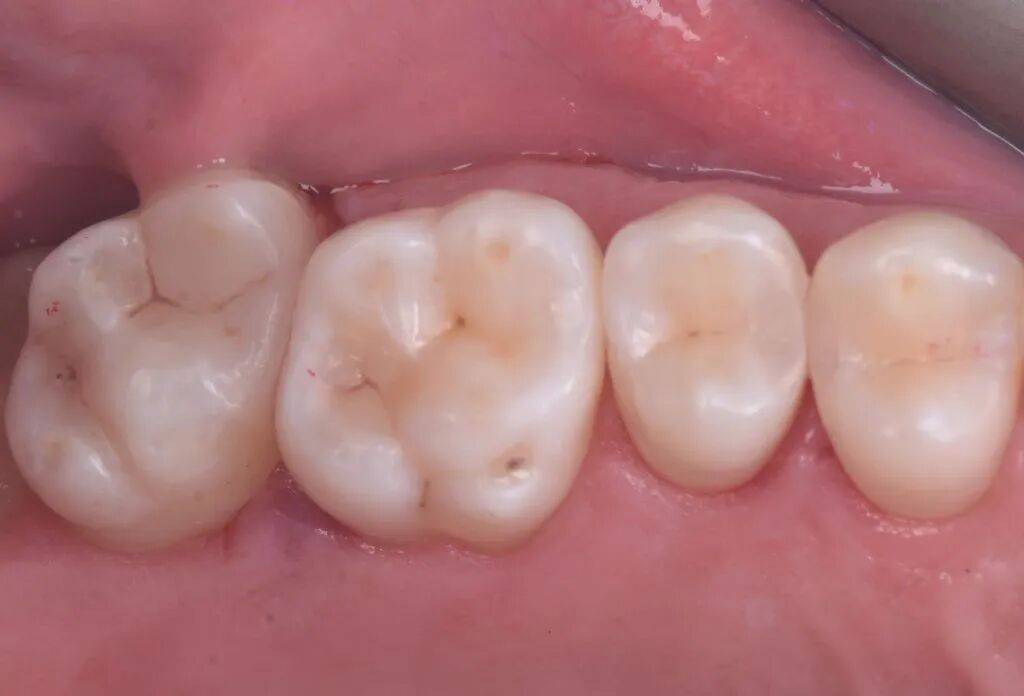

图17. 一个月回访。